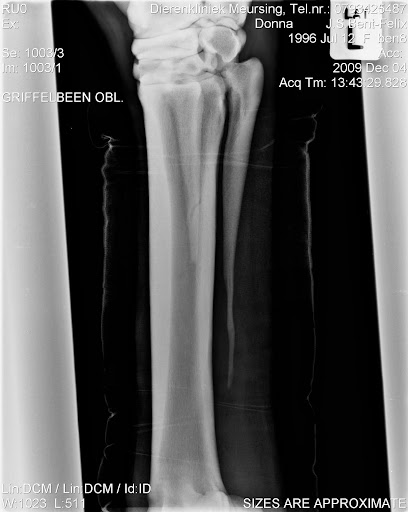

Me meisje is eindelijk weer thuis, na een geslaagde operatie.

De wond ziet er erg netjes uit, na een week mag het verband eraf en dat wordt vervangen voor stalbandages en dan mogen we beginnen met stappen aan de hand, langzaam aan, een maandje rustig aan doen en dan mogen we langzaam aan weer beginnen met opbouwen.